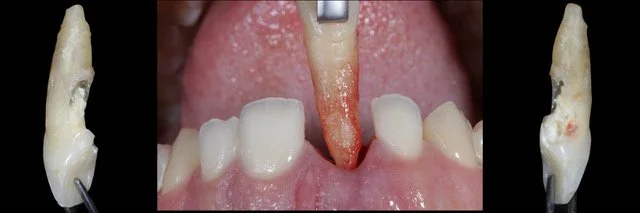

• Tūlītēja, agrīna, atlikta vai vēlīna implantācija?

• No audu saglabāšanas līdz tūlītējās slogošanas protokoliem

16.00 - 18.00 | Tūlītēja implanta ievietošana estētiskajā zonā (#21) un mīksto audu pārvaldība; Digitāli vadīta tūlītēja implanta ievietošana zoba vietā nr. 12 ar horizontālu GBR un CTG, izmantojot diska perforācijas (disc-punch) kaula transplantācijas tehniku. (praktiskās nodarbības Proimplant apmācību telpā Türi 10C Tallinā)